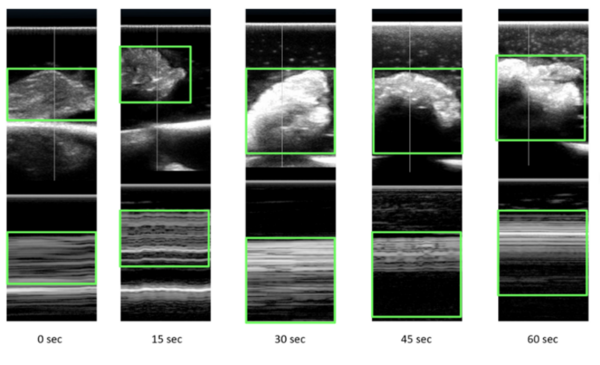

Shariff et al. | Apr 24, 2024

Identification of microwave-related changes in tissue using an ultrasound scan

Image credit: Shariff and Shariff 2024

Microwave energy (ME) is used in the medical field to denature protein structures, resulting in inactivation or destruction of abnormal cells. Identifying the extent of destruction of abnormal tissue (cancer tissue or tissue with abnormal electrical activity) is essential for accomplishing successful therapy and reducing collateral damage. Our study was an ex vivo assessment of the changes on ultrasound scans (US) in chicken tissue exposed to ME. We hypothesized that any changes in tissue structures would be recognized on the reflected ultrasound waves. Ultrasound scans of tissues change with exposure to microwaves with increasing reflection of ultrasound waves. With exposure to microwaves, surface level brightness on the ultrasound scans increases statistically significantly. The findings could be used in heat related (ME and radiofrequency) procedures where clinicians would be able to actively assess lesions in real-time. Further studies are required to assess changes in tissue during active exposure to different types of energies.